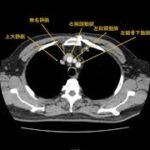

平成31年2月16日②「肺がん手術の変遷と展望」(胸部外科科長兼部長 平田 知己)

第43回埼玉県民のための ”がんの集い”《メインイベント》 平成31年2月16日(土)大宮ソニックシティにおけるがんセンター医師 ......